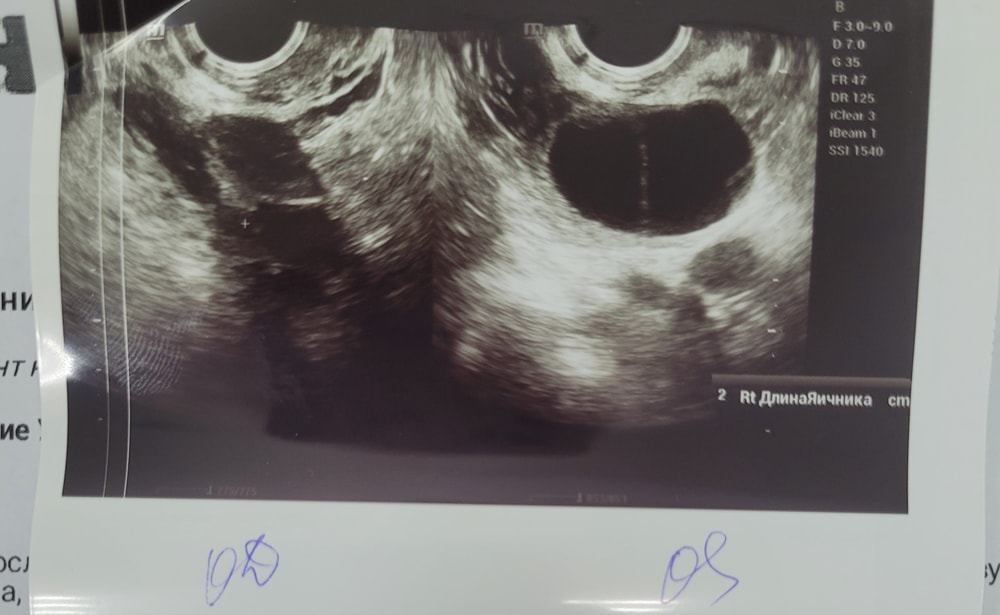

Девочки здравствуйте, подскажите пожалуйста, может было у кого похожее: стимуляция лорета с 4-9 дц, прогинова с 10 дц, сегодня по узи12 дц, эндометрий 10 мм, нашли двухкамерную кисту(((( и никакой овуляции...на 4 дц перед стимуляцией доминантный фолликул был в левом яичнике 11 мм, могло ли созреть рядом два фолликула? просто если посмотреть по снимкам узи на 4 дц и 12дц, как раз похоже, что выросли два фоликула и между ними тонкая полоска...или я просто себя успокаиваю(((((УЗИ на одном и том же аппарате